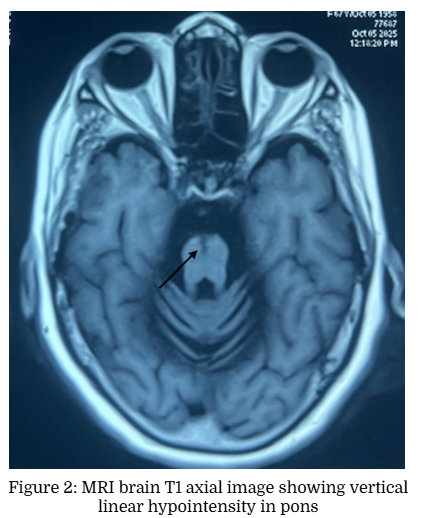

A 67-year-old lady presented with progressive swaying during walking and dysarthria of five years duration. She also noted bilateral upper limb incoordination for the last 2 years. She had occasional falls and urge incontinence. There was no history of any diplopia, dysphagia, weakness, rest tremor or sensory symptoms. There was no history of syncope but had constipation. There was no family history of similar illness. On examination her vitals were normal. Mini Mental Status Examination showed a score of 28 out of 30. Cranial nerve examination showed gaze evoked nystagmus and scanning dysarthria. She had hypomimia with mild bilateral appendicular rigidity. She had normal power in upper and lower limbs with normal deep tendon reflexes. Plantars were flexor. She had bilateral finger nose incoordination and gait ataxia with mild postural instability. Autonomic system examination showed a postural drop of blood pressure of 40/20 mm of Hg. She was treated with carbidopa-levodopa combination without much improvement. In view of symmetrical parkinsonism with poor L-dopa response, bilateral cerebellar signs and postural hypotension, a diagnosis of Multiple system atrophy- cerebellar type (MSA-C) was made and MRI brain was taken. Brain MRI axial T2 weighted images showed Hot Cross Bun Sign (HCBS) and vertical T2 hyperintensity in Pons. There was corresponding hypointensity in T1 weighted images Figure (1 to 4).

The hot cross bun sign (HCBS) is a radiologic finding describing a cruciform T2 hyperintense signal on axial MRI of the pons, classically described in MSA. The underlying pathophysiological process is considered to be atrophy of pontine neurons and transverse pontocerebellar fibers with sparing pontine tegmentum and corticospinal tracts [2]. It is also reported in patients with spinocerebellar ataxia (SCA 1, 2, 3, 6, 7, 8, 10, 17, 23, 31, 34, 42), progressive multifocal leukoencephalopathy, paraneoplastic cerebellar degeneration from a burned-out testicular tumor, leptomeningeal metastases from breast cancer, bilateral middle cerebellar peduncle infarction, cerebrotendinous xanthomatosis, fragile X tremor ataxia syndrome (FXTAS) and variant Creutzfeldt-Jakob disease [3]. HCBS is graded as Grade 0 (No signal changes), Grade 1 (vertical T2 hyperintensity in ventral pons) and Grade 2 (cruciform hyperintensity in pons) in axial T2 weighted MRI brain images [4]. It is reported that the HCBS had a high specificity of 98% to 99% and a high positive predictive value of 94% to 99% for MSA‐C, but the sensitivity was only 45% to 68%. Some of the immune mediated cerebellar ataxia like anti‐Homer 3, anti-Ri and anti Kelch like protein 11 can mimic the MSA‐C phenotype and do not necessarily have a rapid progression [5]. HCBS also has been described in medulla in adult-onset Alexander’s disease [6].